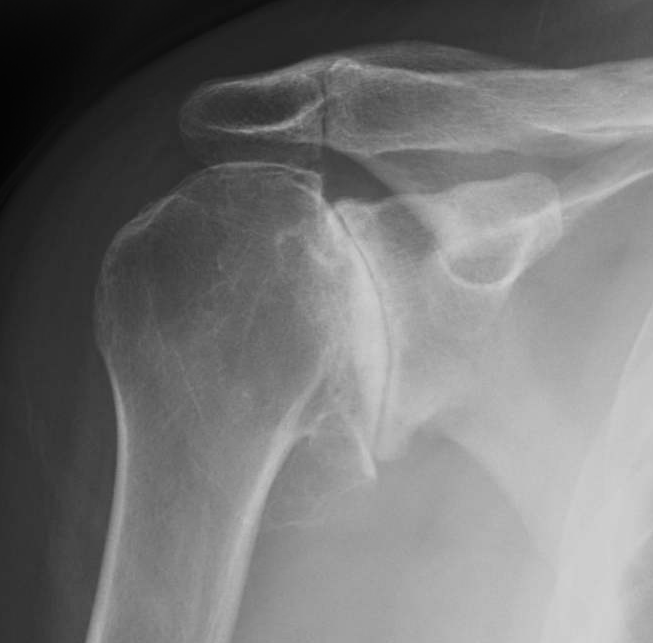

• X-rays: To assess cartilage loss, joint space narrowing, and bone spurs.